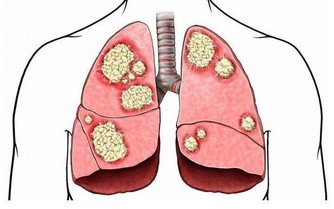

人在睡眠狀態下,由於舌根後墜,使得氣道變窄或者阻塞,氣流通過狹窄部位時,發出來的聲音就叫打呼嚕。

當呼吸道狹窄到一定程度時,會導致呼吸道閉鎖,出現憋氣現象,醫學上稱之為阻塞性睡眠呼吸暫停。呼吸暫停的時間越長,危險越大。

呼吸道通氣功能障礙會導致心臟供氧不足,心臟處於收縮期,可能引發猝死。

若呼吸暫停10秒以上或者在一小時內發生5次及以上時,需及時到醫院就診。